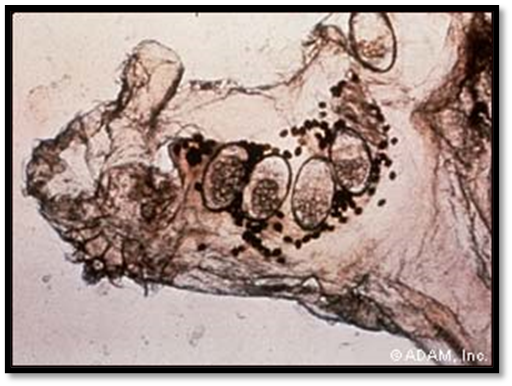

[FIG.1] Scabie Mites, Ova Feces.

The detection of mites, eggs, eggshell pieces, or mite pellets is necessary for a definitive diagnosis. In order to collect multiple superficial skin samples from distinctive lesions, such as burrows or papules and vesicles in the burrow site, a blade should be scraped laterally across the skin, being careful not to cause bleeding. A light microscope operating at low power can be used to examine the specimens  Since potassium hydroxide dissolves mite pellets, it should not be utilized. This method is very operator dependant becausee there are few mites in cases of typical scabies. Scabies is not always ruled out when mites are not found.